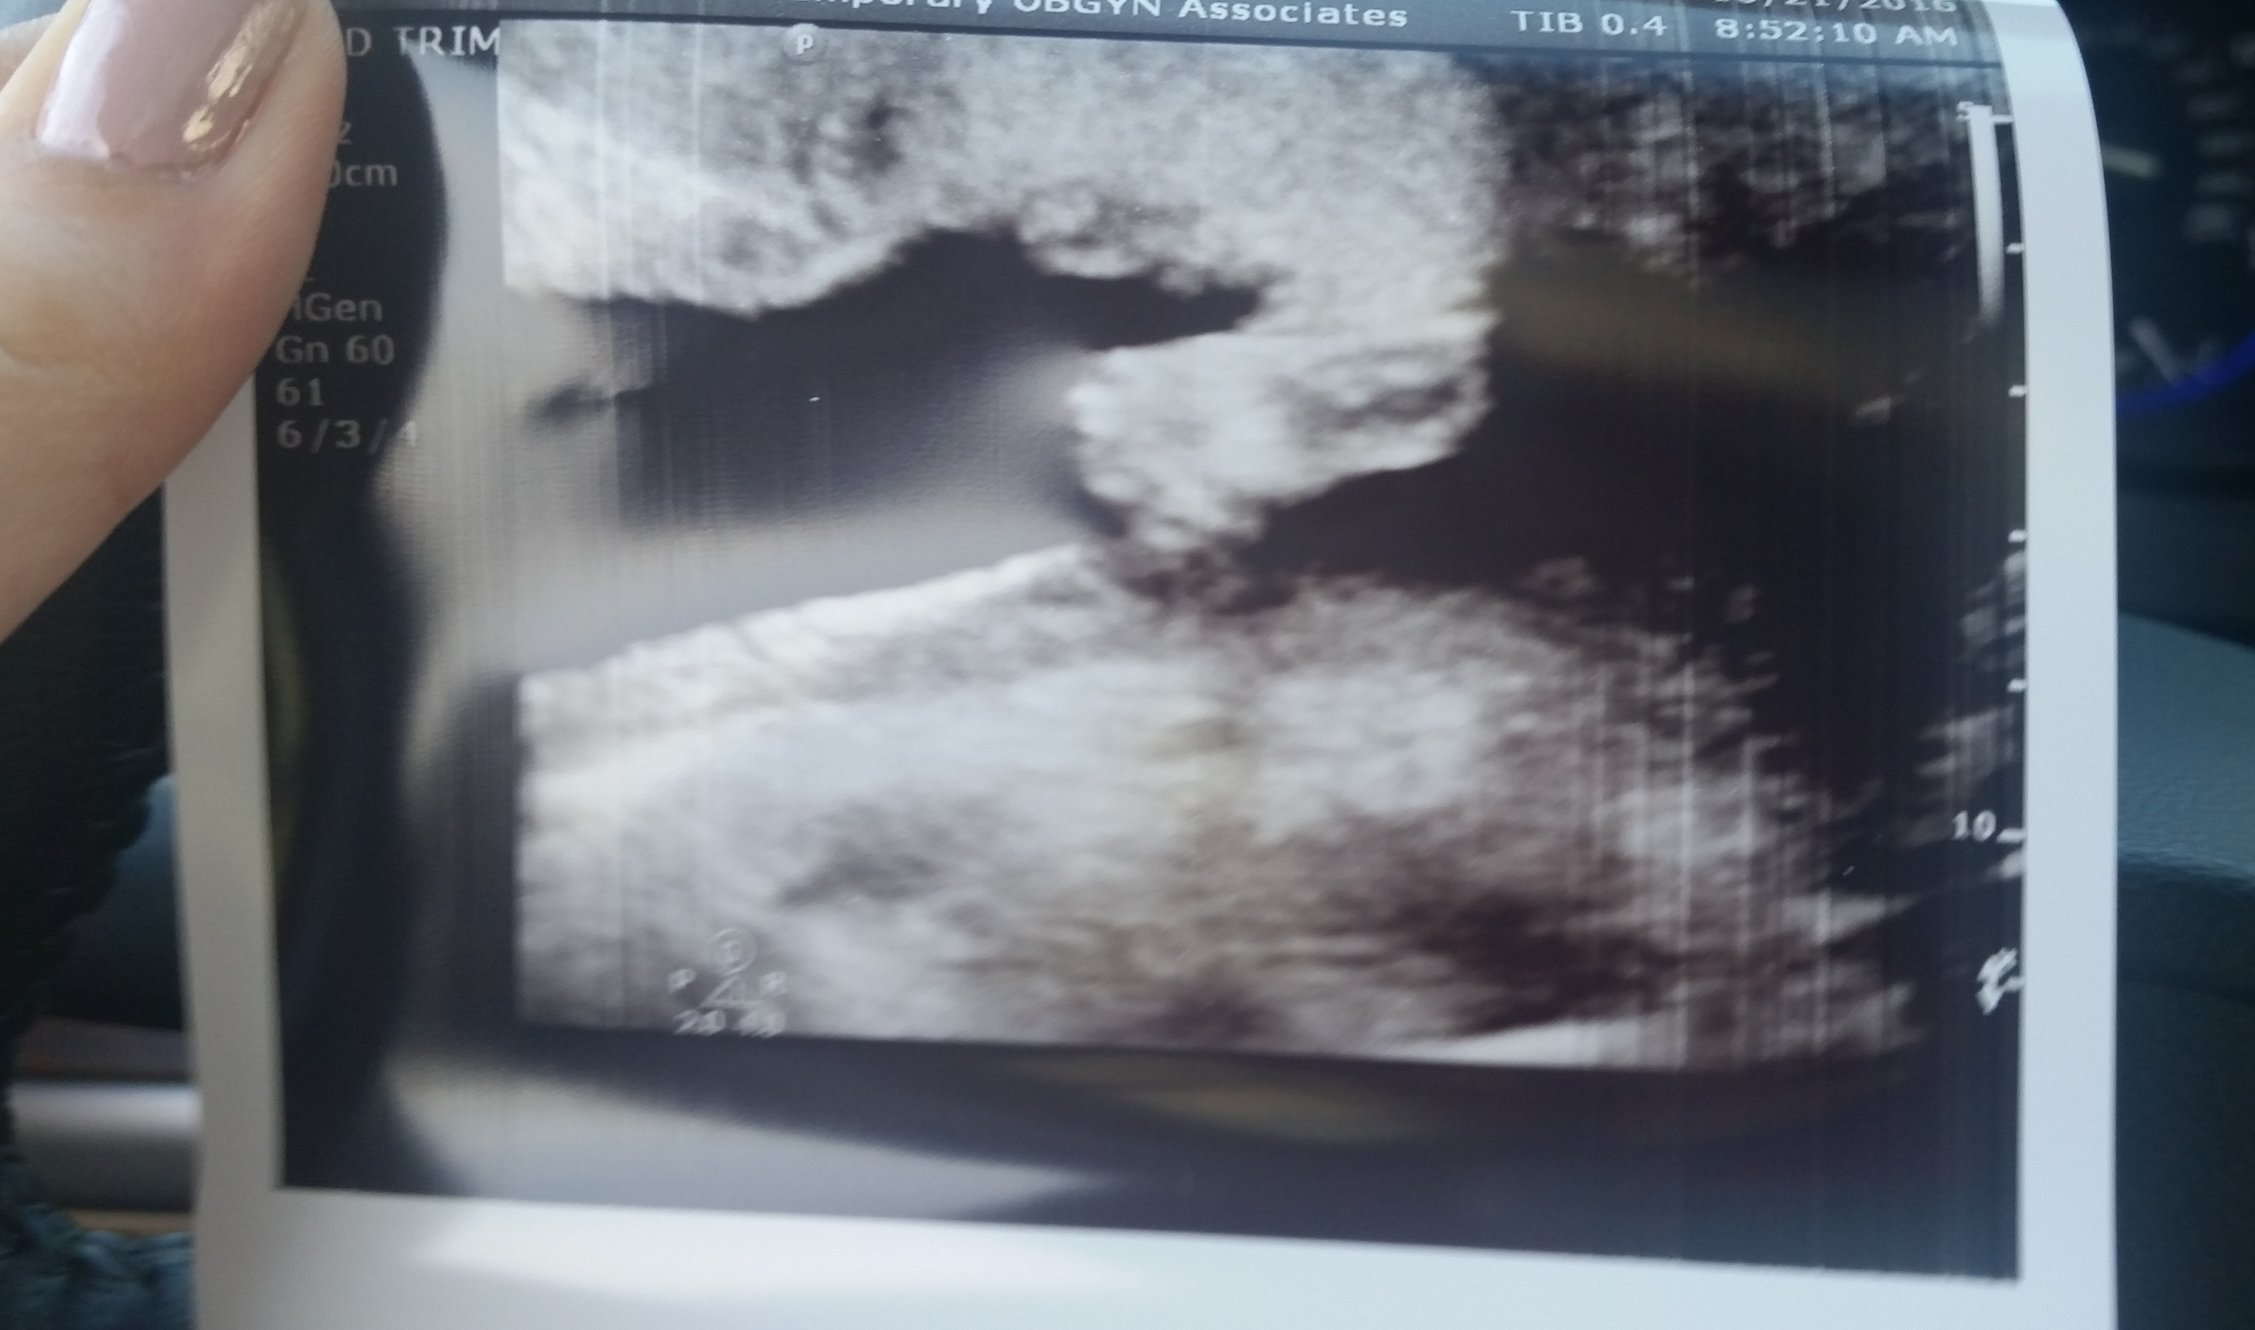

We had our anatomy scan today and also ruled out any complications from a fibroid (which I'm ecstatic about!) I'm so in love with this little face I just had to share! Didn't get any measurements since they were more concerned with the fibroid, but will get all that info at my next appointment.